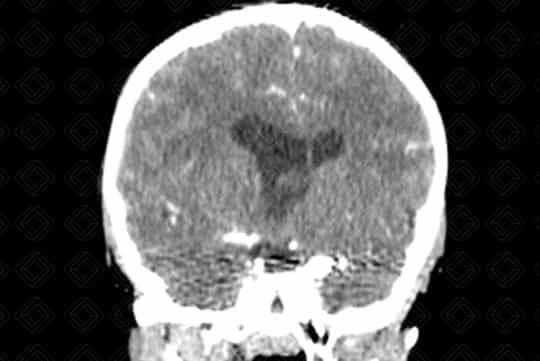

Texto alternativo para a imagem Figura 2. Créditos: Dra. Elazir Mota - Rio de Janeiro/RJ

Descrição das figuras 1, 2, 3, 4 e 5: Tomografia computadorizada do crânio após administração do contraste venoso nas reformatações axial e coronal. Paciente de 4 anos com lesão discretamente captante de contraste (asterisco - figura 2) no corno anterior do ventrículo lateral direito, causando obstrução do forame de Monro e hidrocefalia secundária, de etiologia obstrutiva. [cms-watermark]